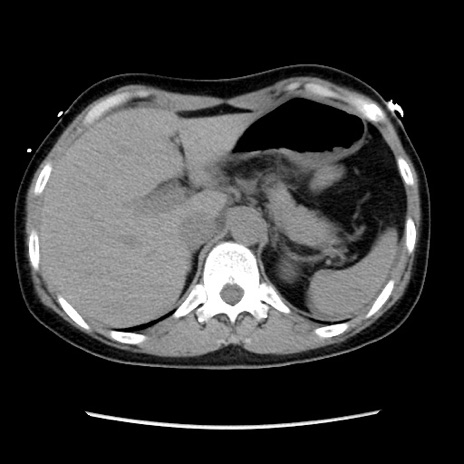

症例10(横断像)

【症例】 50歳代女性

【主訴】 腹痛

【現病歴】前日生レバーを食べた。今朝に排便あり。 昼前に突然発症の腹痛を生じ、当院救急外来を受診した。

【既往歴】 子宮筋腫にてで子宮全摘後

【身体所見】 意識清明、腹部:平坦、軟、下腹部やや左を中心に圧痛・反跳痛あり、筋性防御あり

【データ】WBC 7800、CRP 0.07